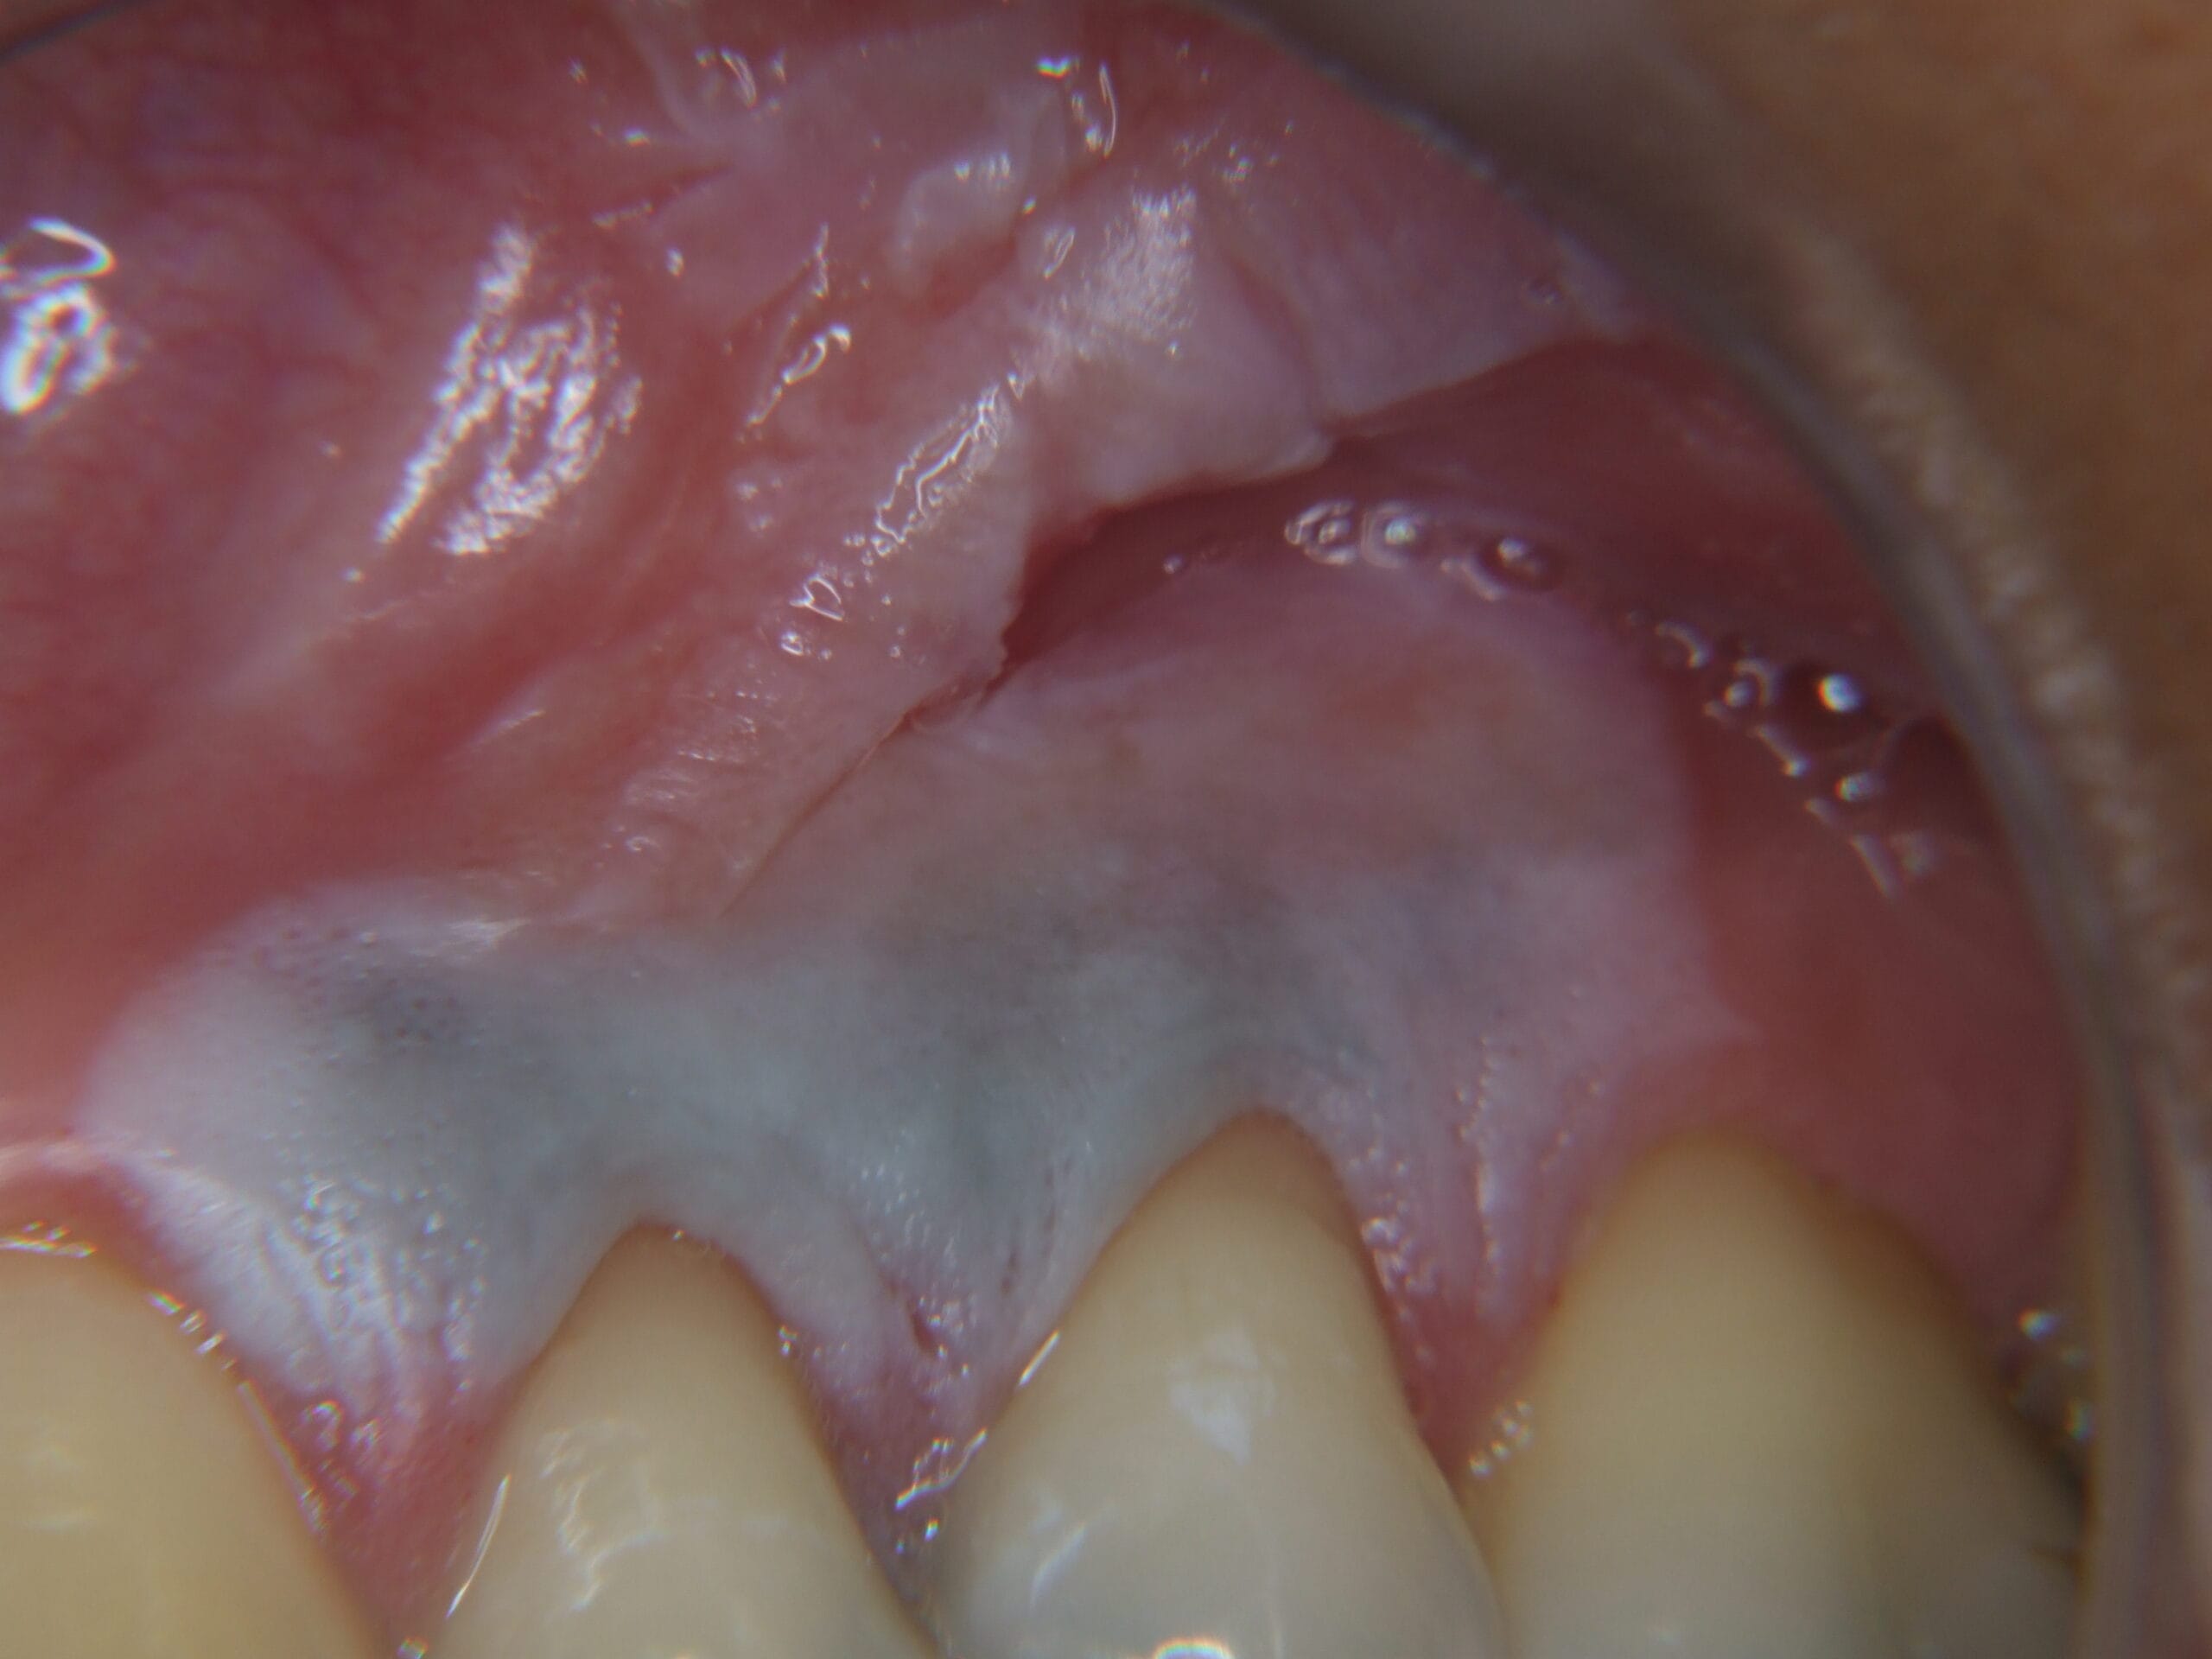

Muitas pessoas pesquisam “remédio caseiro para dor de dente” ou “como aliviar dor de dente rápido”. A própria ADA (Associação Dentária Americana) alerta: colocar aspirina ou qualquer substância diretamente no dente causa queimadura química. Veja casos reais de pacientes que se automedicaram:

Paciente colocou aspirina diretamente sobre o dente. Resultado: queimadura química severa da gengiva.